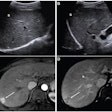

CEUS resolves indeterminate CT, MRI liver observations